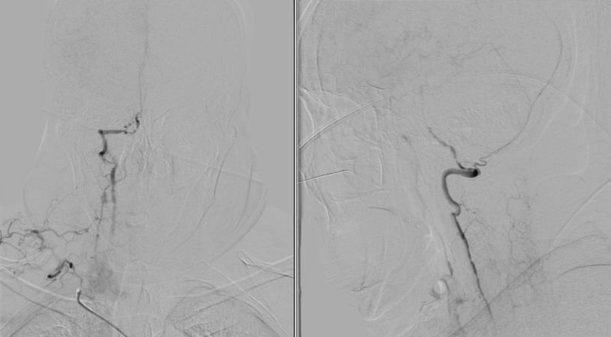

入院影像检查

导丝怎么扩【载药时代 球扩天下】NOVA DES®颅内药物洗脱支架在颈内动脉颅内段重度狭窄中的应用体会二例!_https://www.jmylbn.com_新闻资讯_第20张

导丝怎么扩【载药时代 球扩天下】NOVA DES®颅内药物洗脱支架在颈内动脉颅内段重度狭窄中的应用体会二例!_https://www.jmylbn.com_新闻资讯_第21张

重要影像结论:右侧颈内动脉C4段重度狭窄;右侧颈内动脉C6段中度狭窄;左侧颈内动脉C5段中度狭窄;左侧大脑前动脉A1段重度狭窄。